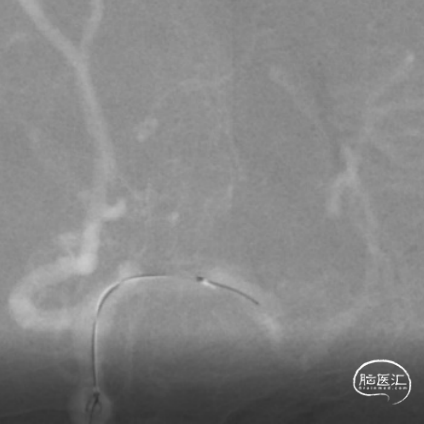

使用Tethys®中间导引导管+DCwire®微导丝通过右侧大脑中动脉M2段闭塞病变处。

微导管造影提示位于血管真腔,3*15mm 支架打开后前向血流未恢复,考虑存在动脉瘤,支架取栓操作有风险,故交换支架予以1.5*15mm 球囊扩张。

为尽快开通血管及处理动脉瘤,选择2.75*20mm 密网支架释放,并予以2.0*15mm 球囊后扩。